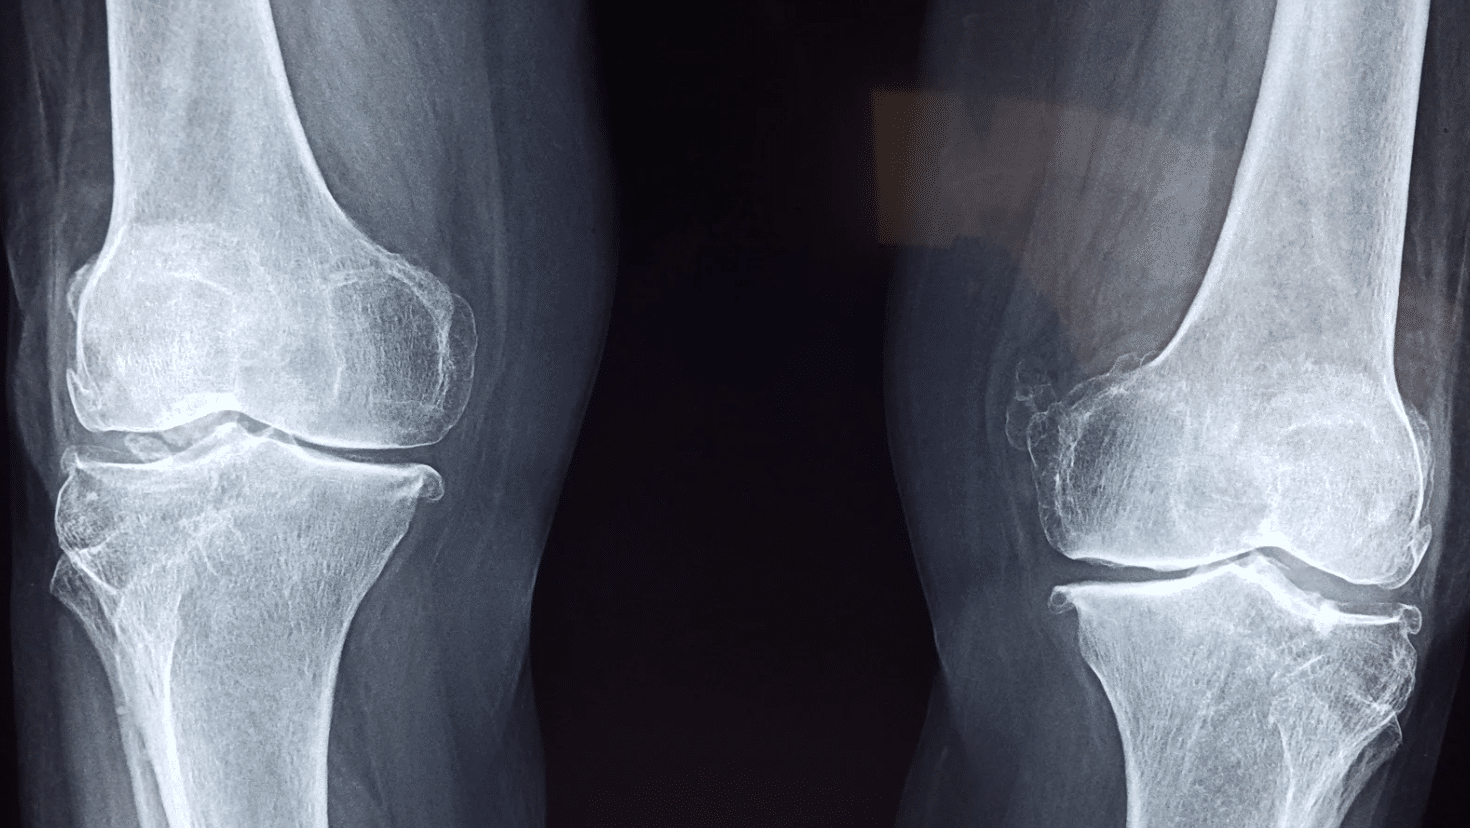

Fractured tibia or fibula

The tibia and fibula are the bones in the lower leg that connect to the knee. If one of these bones breaks in a car accident, it can be a serious injury and may require surgery and a long recovery.